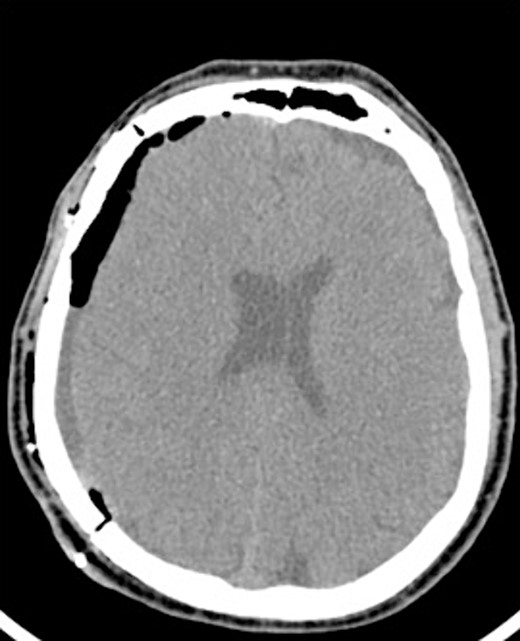

An 81-year-old male with a history of acute subdural hematoma, previously managed non-surgically, presented with worsened confusion and cognitive dysfunction. Repeat CT demonstrated expansion of right-sided subdural collection, consistent with cSDH (Fig. 4).